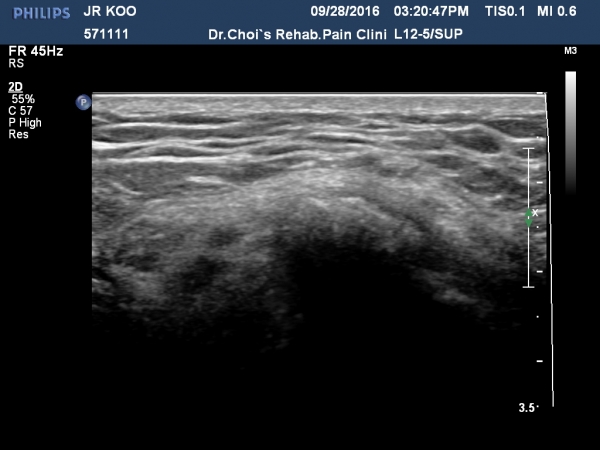

´ëÀüÀÚ È¾´Ü¸é°Ë»ç¿¡¼­ ¼ÒµÐ±Ù¿¡ ¼®È¸È­À½¿µÀÌ °üÂûµÊ(»çÁø 1, 2).